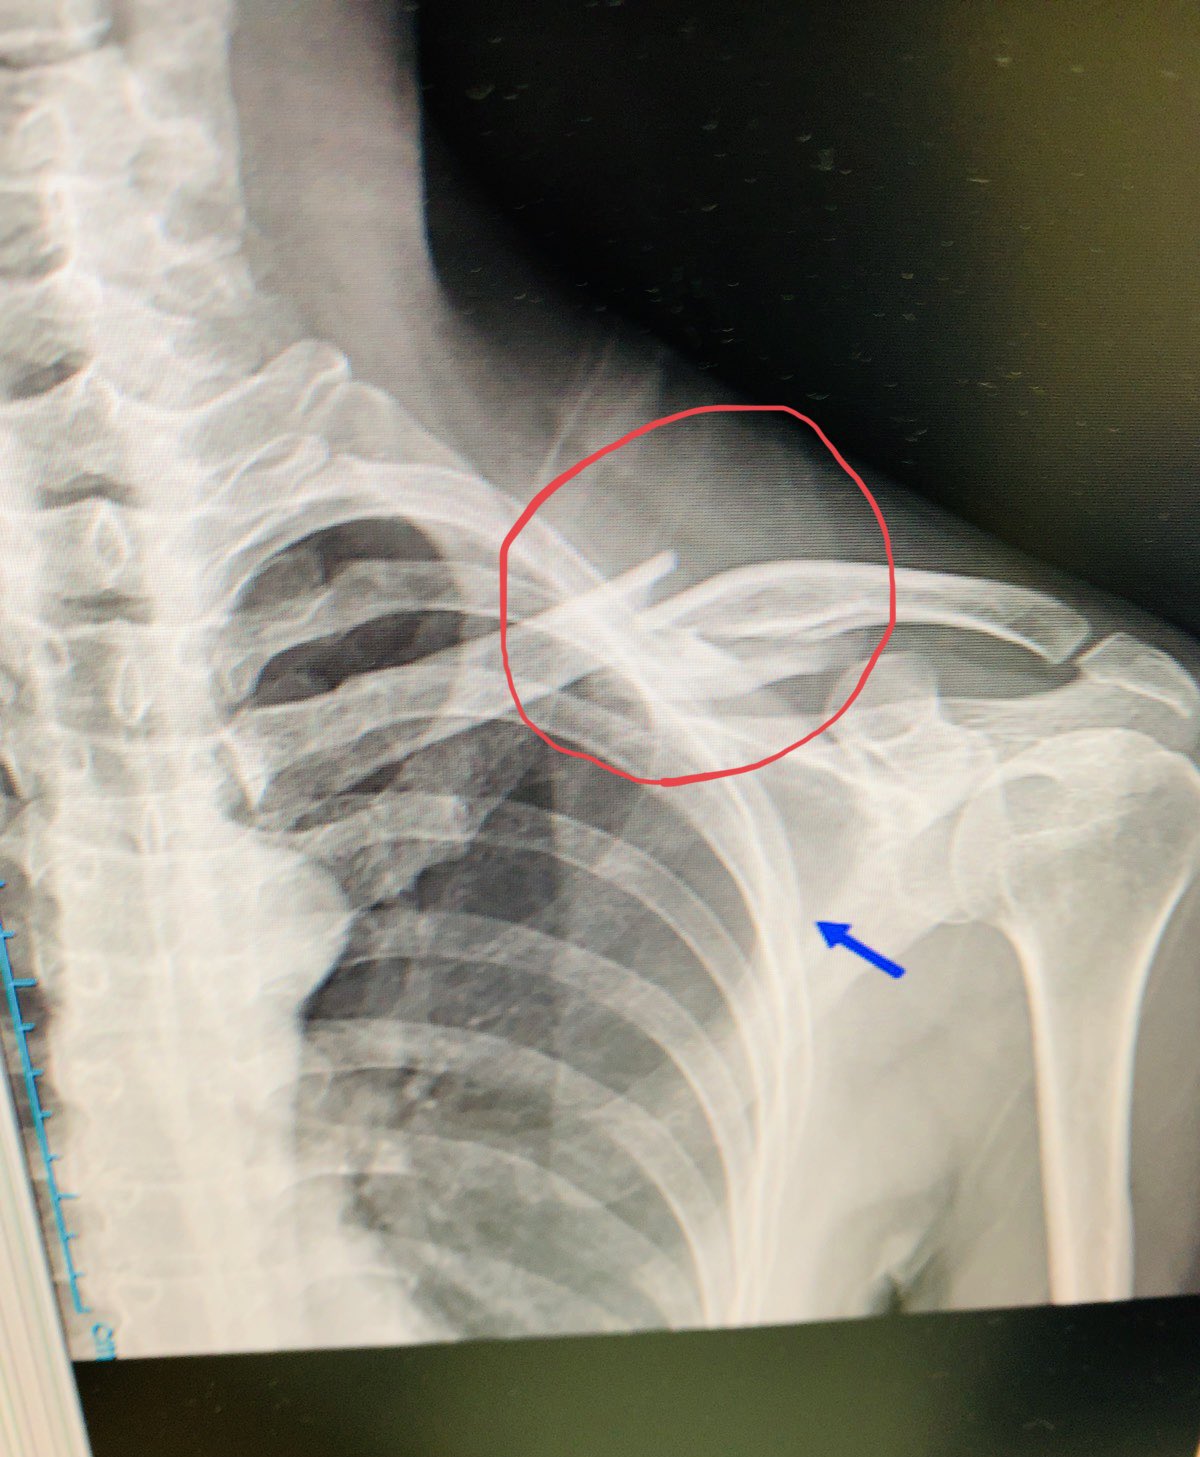

まさくず レントゲン写真 赤丸部分が鎖骨骨折 箇所 正確には4つのパーツに割れている 折れた骨がバラバラにズレているわけではないので手術 プレート固定ではなく 固定バンド装着で治癒することになりました 矢印はドクターからの肋骨もヒビが入っ